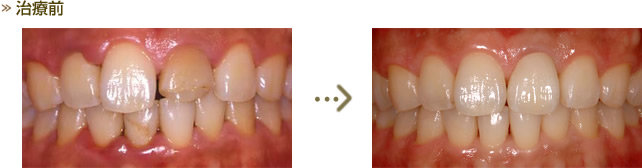

CASE3 審美歯科(オールセラミッククラウン)

治療前・治療後の写真です。 歯周基本治療の後、歯肉のバランスを整えるため左上中切歯のみ歯周外科を行いオールセラミッククラウンで修復しました。